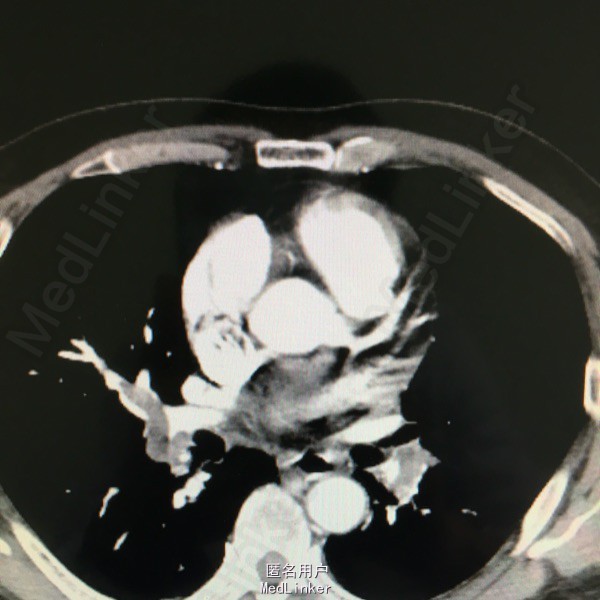

男性,61岁,因气紧3天入院。平时剧烈活动或活动量加大后感气紧。8年前有下肢深静脉血栓,后一直口服阿司匹林。

入院查体见呼吸较平稳,氧饱和度95%左右,嘴唇发紫;CT提示双肺大面积动脉栓塞,心脏彩超提示肺动脉高压,双下肢彩超未见静脉血栓。

慢性肺动脉栓塞,正规抗凝溶栓治疗

对于肺动脉栓塞来讲多数是由于下肢静脉血栓脱落所致,可予以置入腔静脉滤器同时介入下捣栓溶栓。但该患者下肢已无血栓,而且通过症状来看考虑慢性肺动脉栓塞,予以长期正规抗凝治疗十分重要。